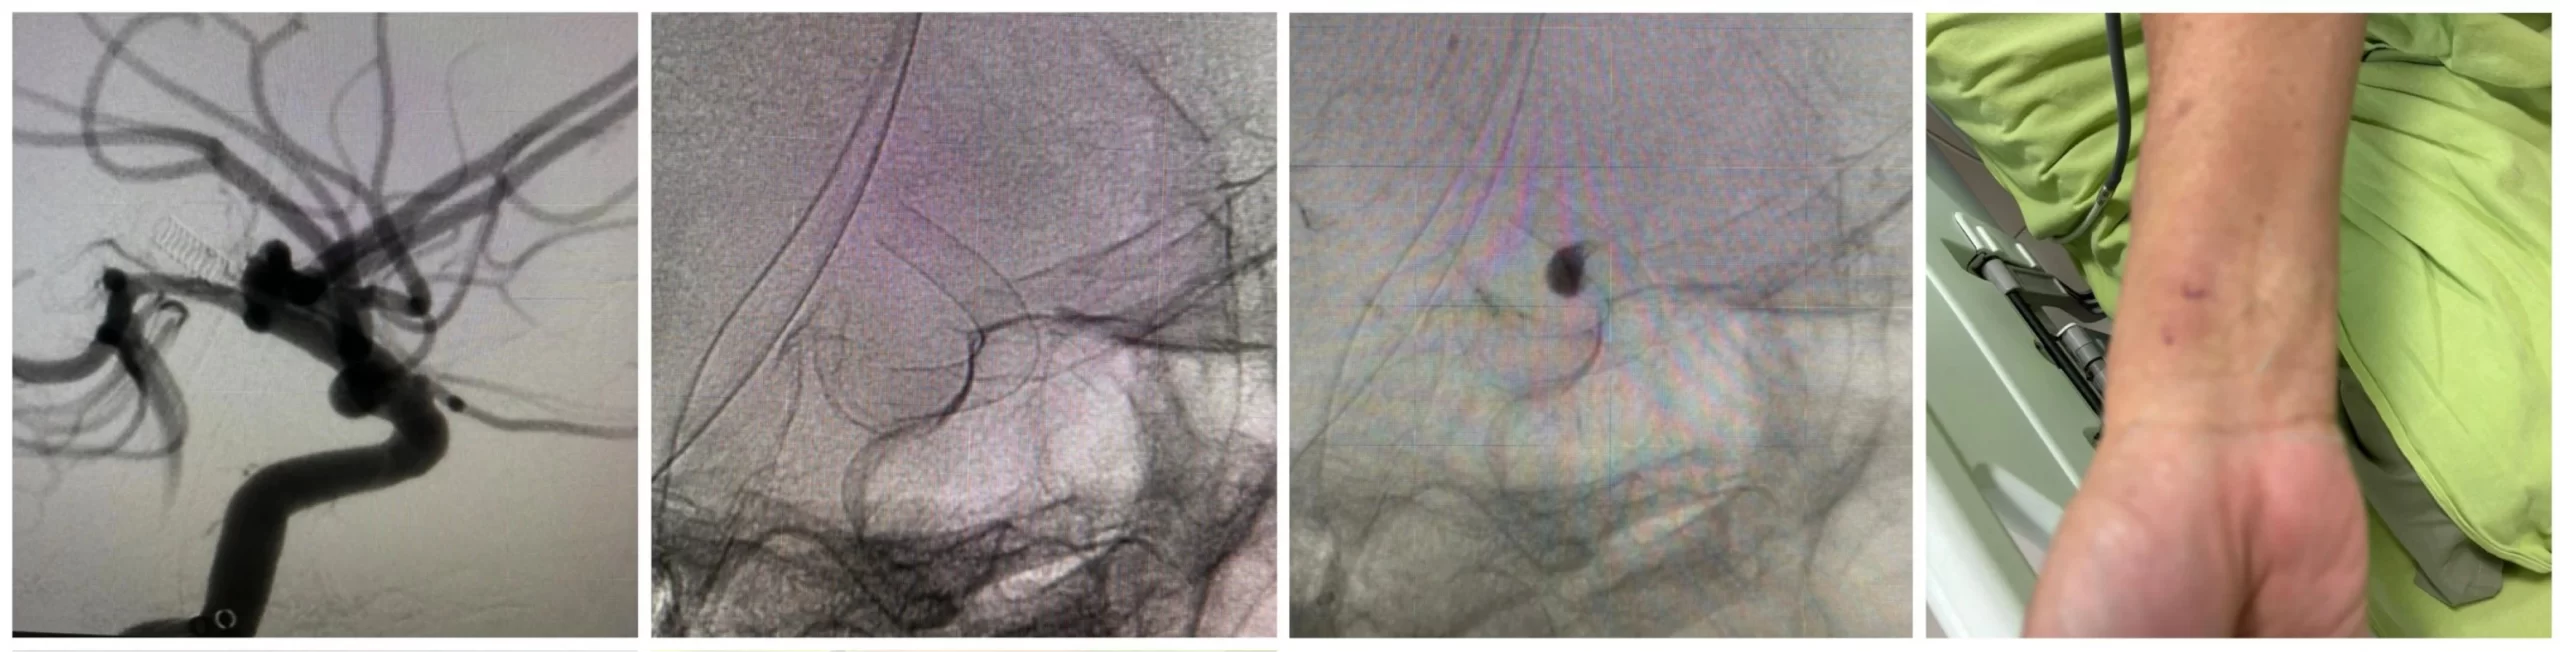

From attending the Medtronic Pipeline with shield technology workshop at Birmingham few years ago to having done the regions first ever trans-radial Pipeline Vantage flow-diverter case at MIOT international Chennai recently, it has been a fabulous flow-diverting journey.

This wide-necked right para-ophthalmic aneurysm on a 65 year old gentleman was treated successfully with a 4.5 x 20 mm Pipeline Vantage trans-radially. Procedure time of 60 minutes. Patient could be mobilized the same evening of procedure and was discharged home in less than 48 hours of elective treatment.